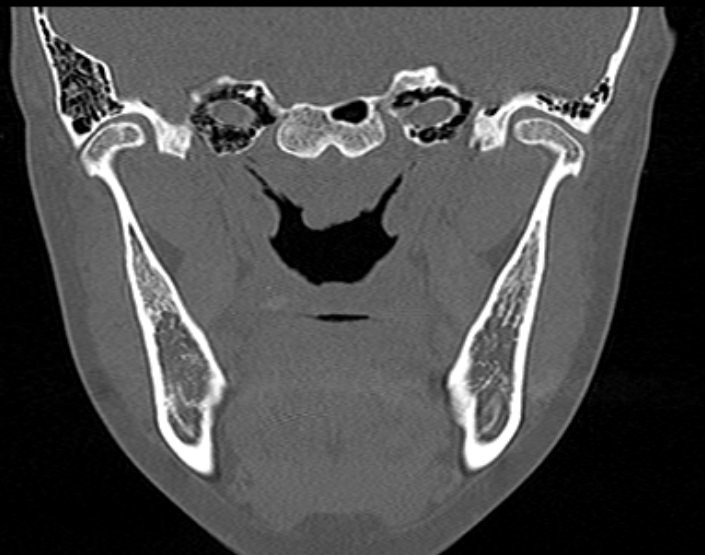

Наиболее точным и информативным методом диагностики костной патологии ВНЧС является мультиспиральная компьютерная томография. КТ относится к лучевым методам исследования, то есть для сканирования применяется рентгеновское излучение. В отличие от обычного рентгена томограф проводит одномоментно множество тончайших срезов исследуемой зоны, которые в дальнейшем проходят цифровую обработку. В результате получаются детальные снимки и трехмерные изображения области височно-нижнечелюстных суставов, которые позволяют проводить точную и достоверную диагностику.

Для оценки функции височно-нижнечелюстных суставов КТ-сканирование проводится в нескольких положениях: с открытым ртом и закрытым ртом. С помощью таких функциональных проб можно оценить положение суставной головки нижней челюсти при движениях нижней челюсти, выявить привычные вывихи и подвывихи суставов.

Компьютерная томография позволяет оценить состояние костных структур височно-нижнечелюстных суставов, так как рентгеновские лучи хорошо задерживаются костной тканью. Для повышения диагностических возможностей компьютерной томографии в ряде случаев дополнительно проводится контрастное усиление путем внутривенного введения йодсодержащего контрастного препарата. Эта методика применяется для улучшения визуализации мягких тканей, которые хуже видны при нативном исследовании.

С помощью КТ можно оценить состояние костной ткани суставных головок нижней челюсти, внутрисуставного мениска, суставной капсулы, связочного аппарата и жевательных мышц.

При проведении мультиспиральной КТ можно выявить следующие патологии височно-нижнечелюстных суставов: